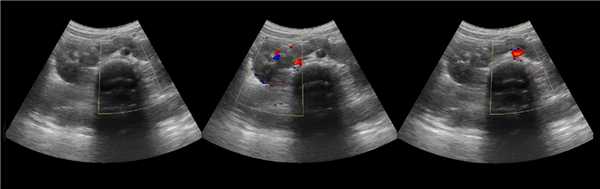

Бывает колонна Бертини врезается в центральную часть почки, разделяя ее полно или неполно на две части. Такая паренхиматозная перемычка — это паренхима полюса одной из эмбриональных долек, которые сливаясь образуют почку; состоит из коры, пирамид, колонн Бертини — все элементы без признаков гипертрофии или дисплазии. Термин гипертрофия колонны Бертини не отражает морфологию структуры, точнее считать данное образование паренхиматозной перемычкой.

Рисунок. На УЗИ округлое образование разделяет почечный синус на два сегмента с общей лоханкой; междолевые артерии огибают образование; эхогенность и интенсивность сосудистого рисунка внутри близка корковой зоне. Заключение: Гипертрофия колонны Бертини или неполная паренхиматозная перемычка. Это вариант нормального строения почки. Термин «неполное удвоение ЧЛК» неверный, т.к. неполная паренхиматозная перемычка не является признаком удвоения ЧЛК.